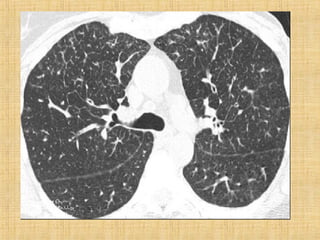

As principais informações do documento são: 1. Discute os padrões de doença pulmonar causados por metástases, incluindo nódulos, espessamento intersticial e obstrução das vias aéreas. 2. A prevalência de metástases pulmonares varia de 30-55% dependendo do tumor primário, e são mais comuns em pacientes acima de 50 anos. 3. Os achados clínicos mais comuns são dispneia, hemoptise e febre, enquanto exames de escarro ou lavado brô